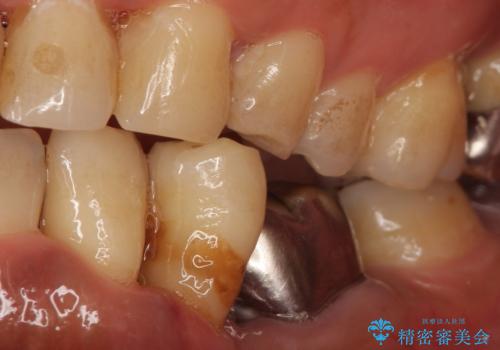

- 左下の歯並びが悪く、左側で物が咬みにくいので診て欲しいといらっしゃった方の症例です。

歯列矯正は御希望されなかったため左下4、5番目の歯を抜歯し、インプラントによる欠損補綴を行いました。

左下6も再根管治療後、オールセラミッククラウンによる補綴を行いました。